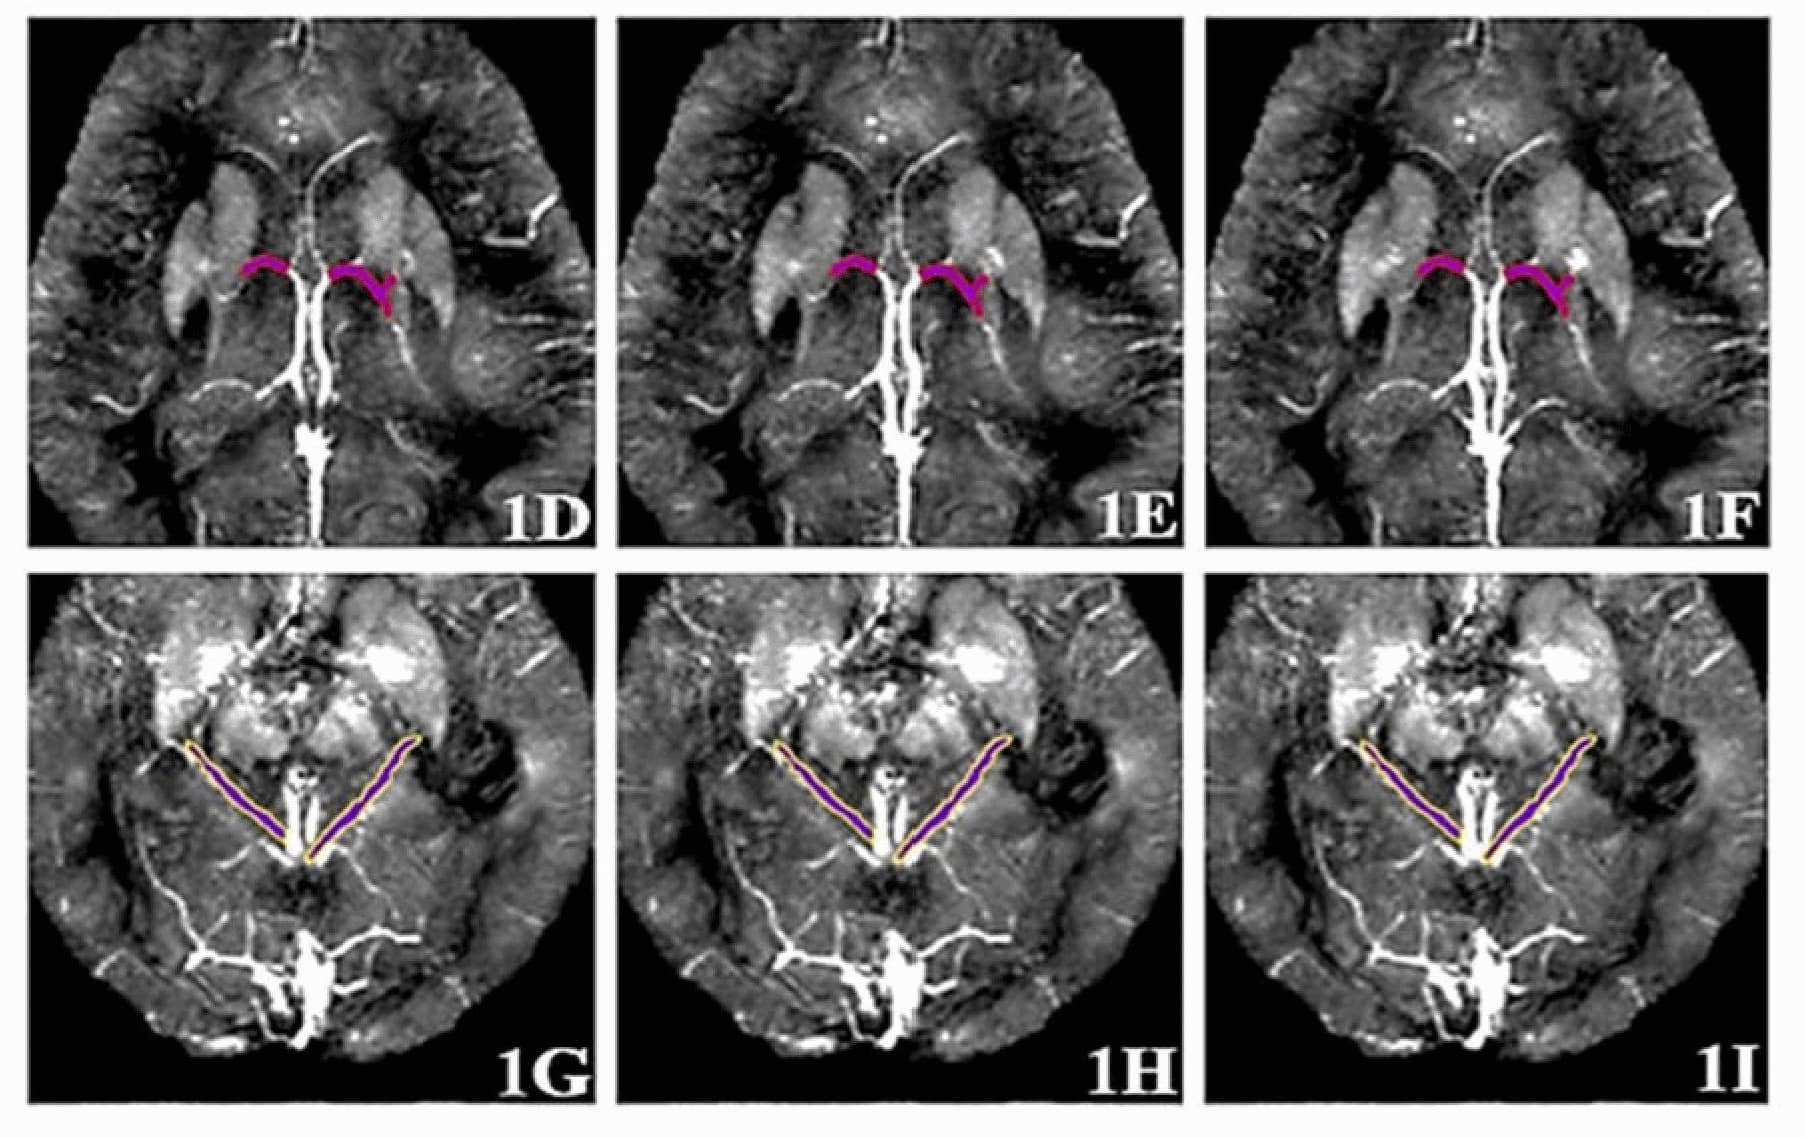

Томографические снимки вен головного мозга

Метод основан на анализе магнитной восприимчивости шести вен головного мозга с помощью МРТ с контрастным усилением. Полученные данные обрабатываются алгоритмом машинного обучения — «деревом решений», которое классифицирует состояние пациента как здоровое (CON) или указывающее на болезнь Альцгеймера (AD).

На практике это выглядит следующим образом. Пациенту вводят контрастное вещество на основе гадолиния, которое усиливает сигнал МРТ, где человек проходит сканирование головного мозга. Далее специалисты измеряют магнитную восприимчивость в шести мозговых венах. Эти параметры дают важную информацию о состоянии кровеносных сосудов и уровнях кислорода, которые могут меняться при развитии болезни Альцгеймера.